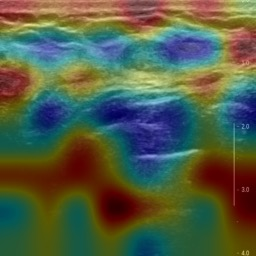

Ultrasonography is an important routine examination for breast cancer diagnosis, due to its non-invasive, radiation-free and low-cost properties. However, it is still not the first-line screening test for breast cancer due to its inherent limitations. It would be a tremendous success if we can precisely diagnose breast cancer by breast ultrasound images (BUS). Many learning-based computer-aided diagnostic methods have been proposed to achieve breast cancer diagnosis/lesion classification. However, most of them require a pre-define ROI and then classify the lesion inside the ROI. Conventional classification backbones, such as VGG16 and ResNet50, can achieve promising classification results with no ROI requirement. But these models lack interpretability, thus restricting their use in clinical practice. In this study, we propose a novel ROI-free model for breast cancer diagnosis in ultrasound images with interpretable feature representations. We leverage the anatomical prior knowledge that malignant and benign tumors have different spatial relationships between different tissue layers, and propose a HoVer-Transformer to formulate this prior knowledge. The proposed HoVer-Trans block extracts the inter- and intra-layer spatial information horizontally and vertically. We conduct and release an open dataset GDPH&GYFYY for breast cancer diagnosis in BUS. The proposed model is evaluated in three datasets by comparing with four CNN-based models and two vision transformer models via a five-fold cross validation. It achieves state-of-the-art classification performance with the best model interpretability.

翻译:超声波分析是乳腺癌诊断的一个重要常规检查,原因是其非侵入性、无辐射和低成本的特性。然而,由于其内在局限性,它仍不是乳腺癌的第一线筛选测试。如果我们能够精确地通过乳房超声图像诊断乳腺癌(BUS),它将是一个巨大的成功。我们提出了许多基于学习的计算机辅助诊断方法,以实现乳腺癌诊断/感官分类。然而,其中多数方法需要事先确定性能模型,然后对ROI内部的跨值进行分类。常规分类支柱,如VGG16和ResNet50等,可以在没有ROI要求的情况下实现有希望的分类结果。但是这些模型缺乏可解释性,从而限制了其在临床实践中的使用。在本研究中,我们提出了一个新的无乳腺癌诊断模型,在超声波图像中进行解释性特征描述。我们利用了先前的解剖学学学知识,即恶性肿瘤和良性肿瘤模型在不同组织层之间有着不同的空间关系,并提议采用状态解析法来编制这一先前的知识。拟议中的HOVer-Trans-Trading-Tradef-trainal Ex-deal-dealal-deal-deal-deal-degraphal-deal-deal-deal-deal-deal-deal disal disal-dal-dal-dal-dal-dal-deal-deal-dal-deal-deal-deal-dal-dal-dal-dal-dal-dal-dal-dal-dal-dal-dal-dal-dal-dal-I-dal-Iversal-dal-Ial-d-d-I-d-d-I-I-I-I-I-I-I-I-I-I-I-I-I-I-I-I-I-I-I-I-I-I-I-I-I-Ial-I-Ial-Ial-I-I-I-I-I-I-I-I-I-I-I-I-I-I-I-I-I-I-I-I-I-I-I-I-I-I-I-I-I-I-I-I-